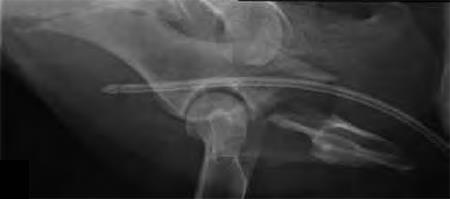

A 4-year-old Gordon setter suffered a road traffic accident and sustained multiple pelvic fractures.

(Case provided by Michael Kowaleski, North Grafton, USA)